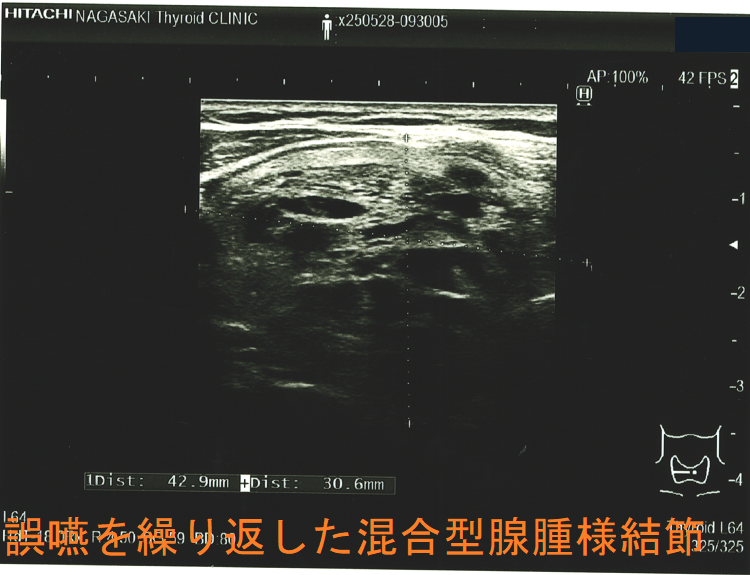

胸骨下まで伸びた巨大甲状腺腫による食道圧迫は、嚥下障害と食道咽頭逆流を生じ、誤嚥性肺炎の原因になります(Korean J Intern Med. 2016 Nov;31(6):1196-1197.)

誤嚥を繰り返した混合型腺腫様結節